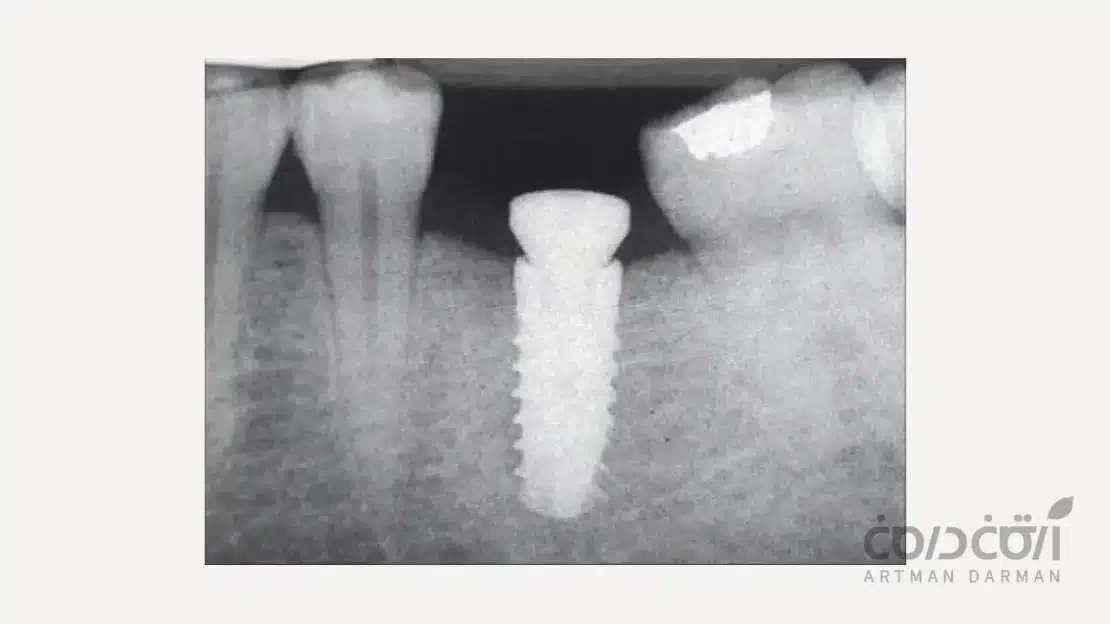

موفقیت درمان ایمپلنت دندان به یک پدیده بیولوژیک شگفت انگیز به نام “اوسئواینتگریشن” (Osseointegration) یا یکپارچگی استخوانی بستگی دارد. در این فرآیند، سلول های استخوان ساز بدن (استئوبلاست ها) مستقیماً روی سطح تیتانیومی ایمپلنت که از نظر زیستی کاملاً سازگار است، رشد کرده و به آن متصل می شوند.

این اتصال مستقیم و محکم، ایمپلنت را به جزئی ثابت و پایدار از استخوان فک تبدیل می کند که قادر است نیروهای شدید جویدن را برای ده ها سال تحمل کند.

برای موفقیت اوسئواینتگریشن به چه میزان توده استخوانی نیاز داریم؟

برای وقوع کامل و موفقیت آمیز اوسئواینتگریشن، ایمپلنت باید به طور کامل توسط حجم کافی از استخوان سالم احاطه شود. حداقل میزان استخوان لازم در اطراف ایمپلنت (معمولاً ۱.۵ تا ۲ میلی متر در تمام جهات) یک استاندارد علمی پذیرفته شده است.